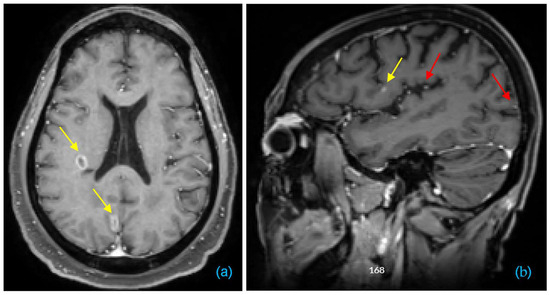

田仲真治「Brain Update」 A single dose of a new brain cancer treatment shrank aの詳細情報

A single dose of a new brain cancer treatment shrank a。All You Need to Know about Brain Tumors - Yashoda Hospitals。J-difference GABA-edited MRS reveals altered cerebello。

田仲真治『BrainUpdate』DVD

Where Does Auto-Segmentation for Brain Metastases